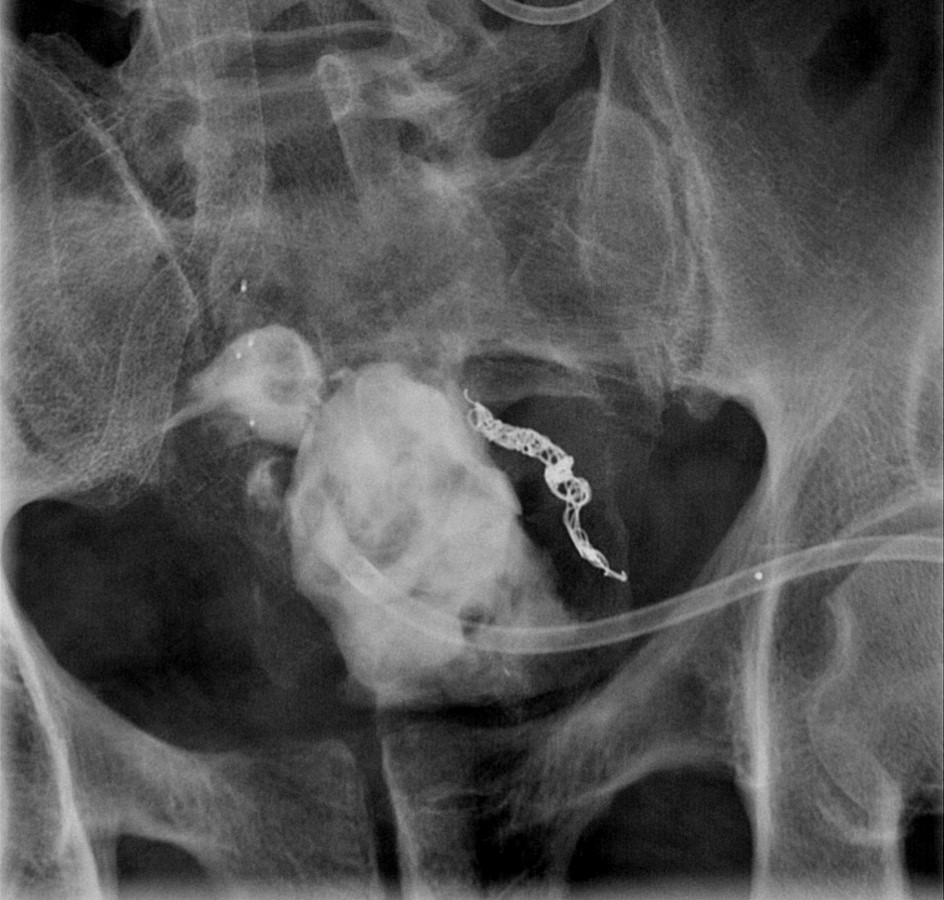

- When reviewing the preliminary scout film, you should see multiple surgical chain sutures in the pelvis

(key image 31)

(key image 32).